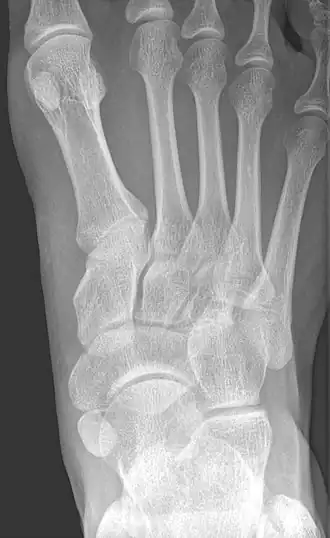

X-ray of the foot showing an accessory navicular bone

An accessory navicular bone is an accessory bone of the foot that occasionally develops abnormally in front of the ankle towards the inside of the foot. This bone may be present in approximately 2-14% of the general population and is usually asymptomatic.[1][2][3] When it is symptomatic, surgery may be necessary.

Radiological images